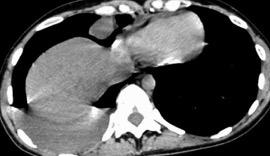

Marzo 2014: Perforación longitudinal distal secundaria a episodio de vómito (síndrome de Boerhaave). Derrame pleural izdo. que evoluciona a empiema.

Wang C-T et al. Tension hydropneumothorax in a Boerhaave syndrome patient: A case report . World J Emerg Med, 2021. Katabathina V et al. Nonvascular, nontraumatic mediastinal emergencies in adults:a comprehensive review of imaging findings. Radiographics. 2011.

30. DERRAME IZQUIERDO. SÍNDROME DE BOERHAAVE